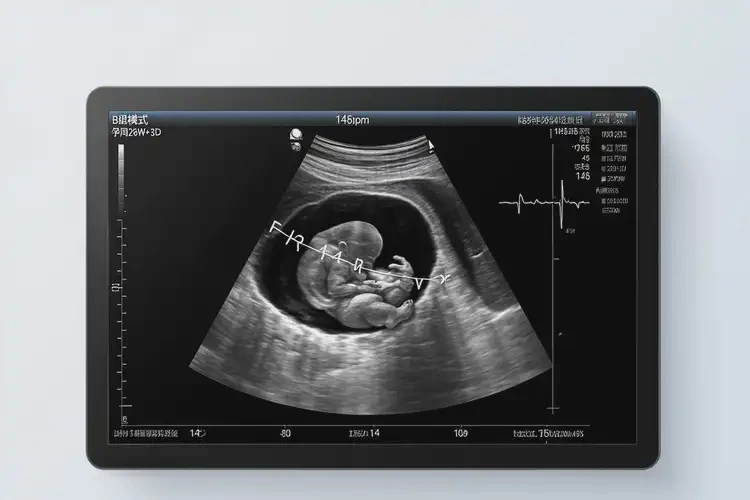

懷孕39周胎心110左右正常嗎(圖1)

懷孕39周胎心110左右正常嗎(圖2)

懷孕39周胎心110左右正常嗎(圖3)

懷孕39周胎心110左右正常嗎(圖4)